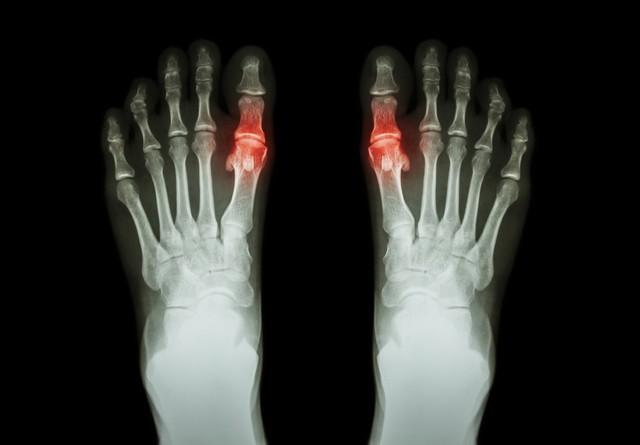

首先是“双轨征”。这是痛风最典型的超声表现之一。在超声图像上,可以看到关节软骨表面附着有不规则的带状强回声,与软骨下方的高回声骨面平行,形成两条回声线,就像铁轨一样。这种表现是由于尿酸盐结晶沉积在关节软骨表面所致。

其次是痛风石。在超声图像中,痛风石表现为混杂的高、低回声团块,内部回声不均匀,可能伴有或不伴有血流信号。早期痛风石质地较软,体积较小,而晚期痛风石质地变硬,体积增大,后方可能伴有声影。

此外, 超声检查还能观察到关节积液、滑膜增厚、点状强回声等表现。 关节积液表现为关节腔扩张,内有可移动的液性暗区。滑膜增厚则表现为难以被超声探头压缩的低回声或无回声区域,可能伴有血流信号。点状强回声是指尿酸盐结晶沉积在滑膜上形成的高回声点,如果晶体弥漫聚集,还会出现“暴雪征”样的改变。